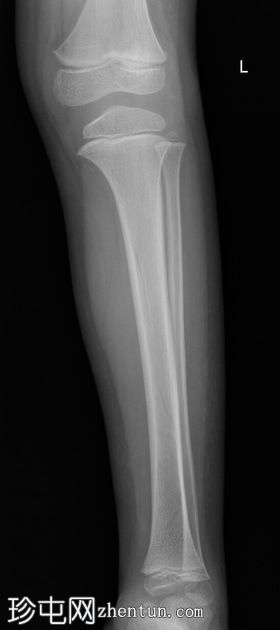

左腿及踝关节

X线片

侧位

胫骨远端骨干可见一条螺旋状透亮线,提示骨折(正位、侧位)。

应用锐化算法并放大正位片(骨折由近端向远端)和侧位片。

幼儿骨折是指幼儿因扭转(足部着地时股骨内旋)导致的胫骨中远端轻微移位的螺旋状骨折,这种情况可能发生在儿童绊倒时。患者接受了6周的石膏外固定治疗。

请注意,应用锐化骨算法并放大图像后,骨折及其范围会更加清晰可见。